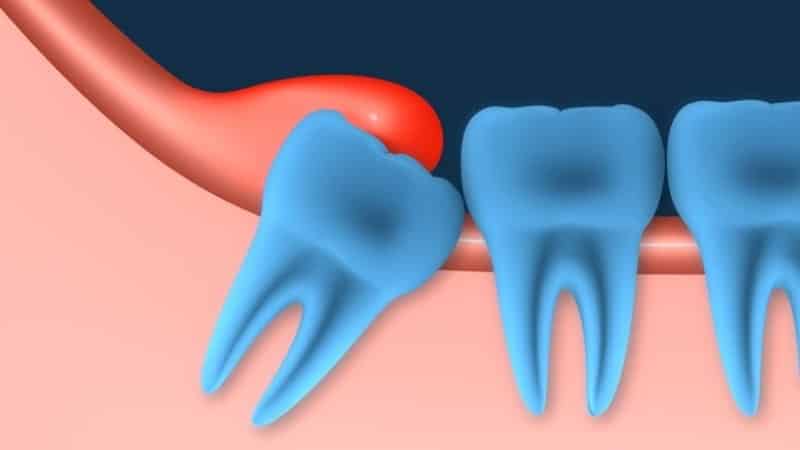

Зубы мудрости, или третьи моляры, часто имеют аномалии в расположении или направлении роста, что может вызывать дискомфорт. Их рост зачастую происходит под неправильным углом относительно других зубов и челюсти, что может приводить к тому, что они упираются в соседние корни или щеки. Зачастую еще до их появления наблюдаются боли в деснах и отечность в местах, где они должны прорезаться. Причины этого могут быть связаны с анатомическими особенностями.

При наличии патологий в зачатке зуба мудрости он может прорезываться и расти долго, сопровождаясь острой болью и неполным выходом коронки над десной. Это может привести к нарушению прикуса, а также к разрушению соседних зубов и их скученности.

Одним из наиболее распространенных осложнений, возникающих в процессе роста зубов, являются воспалительные процессы в деснах, расположенных рядом с зубом. В этот период на поверхности десны может образовываться бугорок, который покрывается слизистой оболочкой, известной как капюшон. Это образование подвержено травмам и механическим повреждениям, особенно при употреблении твердой пищи, что способствует активному размножению вредных микроорганизмов и бактерий, а также может привести к нагноению.

Такие образования могут свидетельствовать о перикоронарите — заболевании, которое начинается с легких болей в области прорезывания зуба мудрости. По мере прогрессирования воспалительного процесса боль усиливается, отдавая в виски, уши, а также при глотании и открывании рта. Возможны также боли в лицевых мышцах, воспаление тройничного нерва и лимфатических узлов, иногда наблюдается повышение температуры и головная боль. Отечность и покраснение в области капюшона могут сопровождаться выделением гноя.